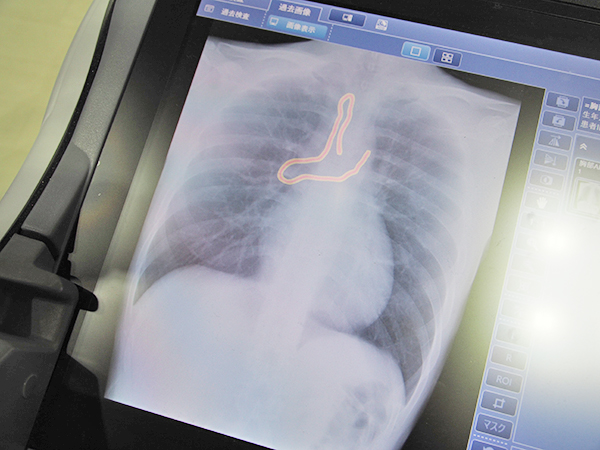

回診用X線撮影装置向けに開発された“遺残確認支援ソフトウエアSmart DSI”は,AIの深層学習を用いて,外科手術直後に行うX線撮影による異物遺残確認を支援し,効率的なチェックを可能にする。X線画像診断装置のワークステーション用プログラム「AI-Station」の機能として提供され,まずは回診用X線撮影装置「MobileDaRt Evolution MX8 Version cタイプ」に搭載可能となった。ガーゼや縫合針,鉗子など,人体以外の可能性があるものを色を付けて強調表示することで,骨と重なった領域などでも見逃しのリスクを低減し,医療従事者の負担を軽減する。処理画像は,撮影後にボタンを押して表示,または撮影後に自動表示され,スムーズなワークフローの中で利用できる。

“遺残確認支援ソフトウエアSmart DSI”によるガーゼの検出